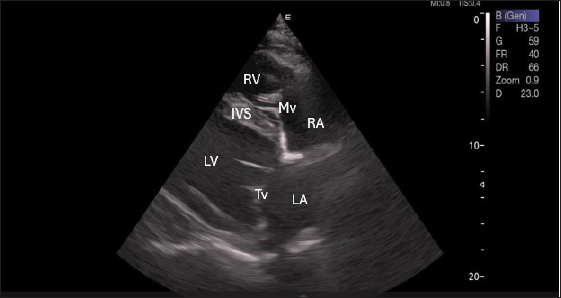

Left parasternal ultrasonography

Figure 5 shows an image of the ventricles, atria, and interventricular septum in the caudal long-axis four-chamber view acquired by positioning the probe perpendicularly in the fourth intercostal space or longitudinally in the fifth intercostal space with a little clockwise rotation. Every camel had a perfectly normal heart anatomy, including ventricles, tricuspid valve, mitral valve, and atria on both sides. During the fourth ICS image of the LVOT, the probe was turned slightly further cranially and twisted somewhat counterclockwise (Fig. 6). No camel is complete without an oblique aortic cross-section.

Fig. 5. Left parasternal longitudinal axis (Systole) of 16 years racing camel showing Lv=left ventricle, Rv=right ventricle, Ivs=interventricular septum, Mv=mitral valve, and Tv=tricuspid valve.